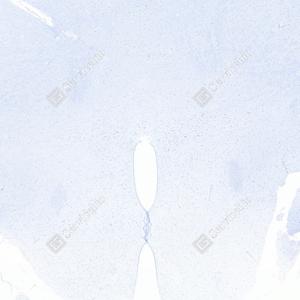

| IHC检测c-Fos蛋白(货号 GB15069). 样品: 大鼠MACO模型脑组织, 4%多聚甲醛 (货号G1101) 固定12-24小时. 抗原修复: Tris-EDTA抗原修复液(pH 9.0) (G1203), 98℃, 20分钟. —抗: 1: 1000稀释, 4℃ 孵育过夜. 二抗: S-vision免疫组化多聚二抗(山羊抗兔),即用型 (货号G1302), 室温孵育20分钟. |